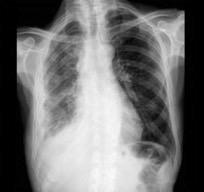

Marzo 2014: Perforación longitudinal distal secundaria a episodio de vómito (síndrome de Boerhaave). Derrame pleural izdo. que evoluciona a empiema.

Wang C-T et al. Tension hydropneumothorax in a Boerhaave syndrome patient: A case report . World J Emerg Med, 2021. Katabathina V et al. Nonvascular, nontraumatic mediastinal emergencies in adults:a comprehensive review of imaging findings. Radiographics. 2011.